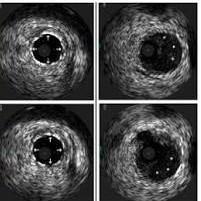

Intra-vascular ultrasound(IVUS) is a critical high resolution imaging modality in cardiologynused to visualize the interior of the coronary arteries providing 360 degree cross sectional view of the vessels.

It surpasses traditional angiography by allowing physicians to measure vessel dimensions, characterize plaque, and guide stent placement, particularly in complex cases like left main diseases, bifurcations, and chronic total occlusions. Recent studies show that IVUS-guided PCI (Percutaneous Coronary Intervention) significantly reduces major adverse cardiovascular events (MACE), including mortality and stent thrombosis

Plaque Characterization: Identifies the type of plaque (calcified, soft, lipid-rich) to determine the need for pretreatment with plaque modification tools like atherectomy.

Stent Optimization: Ensures proper stent expansion and apposition (adhesion to the vessel wall), reducing the risks of stent thrombosis or restenosis.

IVUS vs. Angiography: While angiography shows a 2D shadow of the lumen, IVUS shows the 3D vessel structure.

IVUS vs. OCT (Optical Coherence Tomography): IVUS provides better penetration to see through plaque and in large vessels, while OCT has higher resolution but limited penetration and requires blood clearance with contrast.

High-Definition (HD) IVUS: New 60 MHz transducers offer superior resolution (under 40 μm) to visualize thin-strut stents, bridging the gap between traditional IVUS and OCT